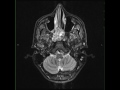

Juvenile Angiofibroma

28-year-old male presents for long standing nasal obstruction with recurrent epistasis. There is a T1 heterogeneous but predominantly isointense, T2/STIR heterogeneously hyperintense solid and cystic mass with avid enhancement arising from the level of the sphenopalatine foramen with chronic osseous remodeling of the sphenoid bone as well as involving the posteromedial walls of the maxillary antra bilaterally. There is destruction of the posterior nasal septum. Prominent flow voids are noted throughout. Imaging findings are most compatible with a juvenile nasopharyngeal angiofibroma. Juvenile nasopharyngeal angiofinroma are benign but locally agressive tumors occuring almost exclusively in males. Typical age at presentation is adolescence. They are the most common benign nasopharyngeal neoplasm. Treatment is with complete surgical resection, typically in conjunction with preoperative embolization. Involvement of the skull base increases likelihood of tumor recurrence to 50%.